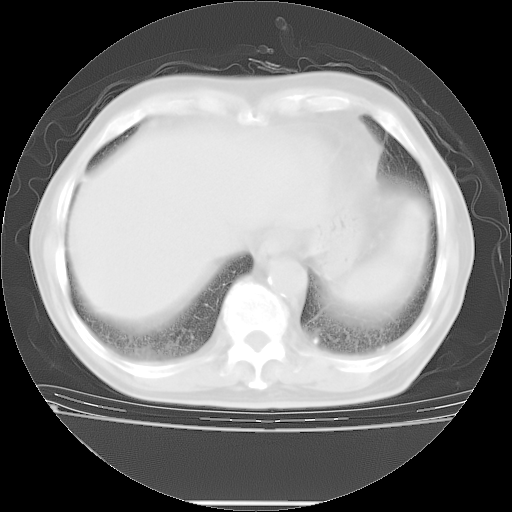

今天复查肺部CT,发现双肺广泛磨玻璃样改变。所以我把3月19日和5月9日相隔50天的肺部CT上传。请大家会诊。

5月9日肺部CT(在4月27日齐鲁医院肺部CT描述部分肺组织磨玻璃样改变,12天后肺组织广泛磨玻璃样改变)

2009年5月9日肺部CT

大致读了系列胸部CT:纵隔窗无明显异常,肺窗:从4、27至今:主要是双肺中下野外带可见毛玻璃样改变,目前处于急性肺泡炎阶段,至于原因考虑1、结替组织或胶原血管性疾病所致?2、恶性疾病如恶组在肺部所致的表现或细支气管肺泡癌?3、药物或其它原因如肺蛋白沉着症所致肺泡炎目前不太可能?总之,明天就去请我院的呼吸科、感染科、血液科和临免专家会诊哈。